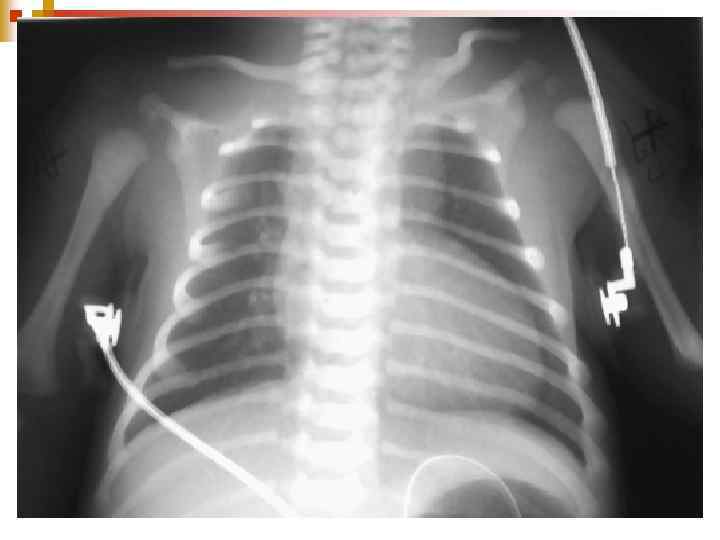

Ventricular septal defect, large left to right shunt

Диагностика При рентгенологическом исследовании органов грудной клетки описывают форму сердца и состояние легочного рисунка, определяют размер кардиоторакального индекса (КТИ). Все эти показатели имеют свои особенности при разных степенях лёгочной гипертензии. В первой, гиперволемической стадии, выявляется сглаженность талии и погруженность верхушки сердца в диафрагму, увеличение КТИ. Со стороны легочного рисунка отмечается его усиление, нечеткость, размытость. Крайней степенью гиперволемии в лёгких является отёк лёгких. В переходной стадии лёгочной гипертензии отмечается нормализация лёгочного рисунка, некоторая стабилизация размеров КТИ. Для склеротической стадии лёгочной гипертензии характерно значительное увеличение размеров сердца, причем в основном за счёт правых отделов, увеличение правого предсердия (формирование прямого атрио-вазального угла), выбухание дуги лёгочной артерии (индекс Мура более 50%), приподнятость верхушки сердца, которая образует с диафрагмой острый угол. Со стороны лёгочного рисунка часто описывается симптом «обрубленного дерева» : яркие, чёткие, увеличенные корни, на фоне которых лёгочный рисунок прослеживается только до определённого уровня. На периферии имеет место признаки эмфиземы. Грудная клетка имеет вздутую форму, ход ребер горизонтальный, диафрагма уплощена, стоит низко.